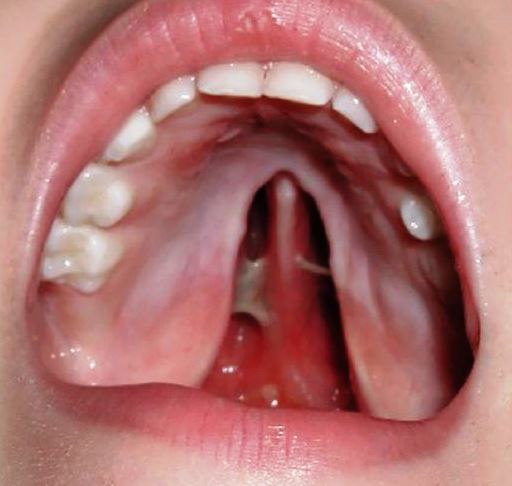

Волчья пасть

• Волчья пасть у детей может быть незаметна при внешнем осмотре новорожденного. Однако, заглянув в ротовую полость можно заметить вертикальное отверстие в тканях верхнего неба. Такие малыши уже с первых секунд жизни испытывают проблемы с дыханием и сосанием и получают всю необходимую помощь.